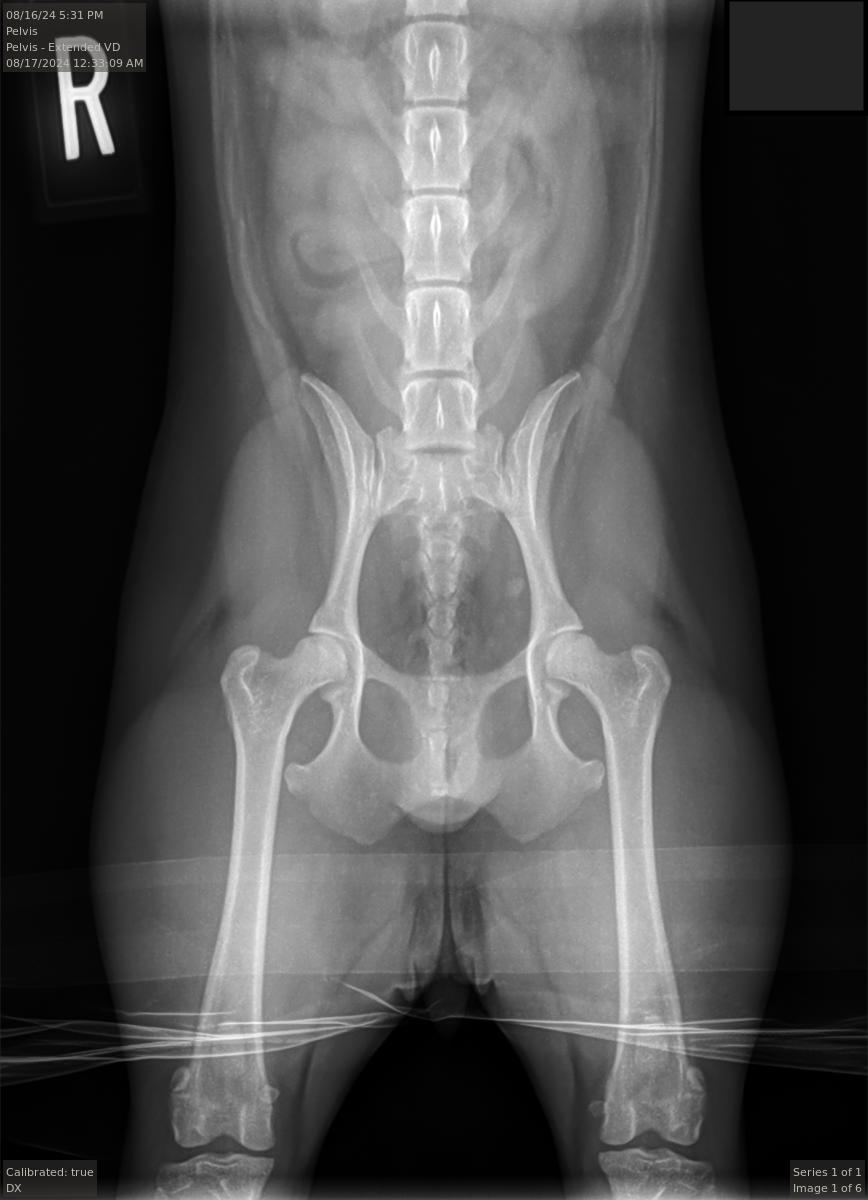

OFA|PennHIP|Patella|Shoulder

OFA Hip Rating:

Good

PennHIP Rating:

Right DI 0.41 | Left DI 0.34